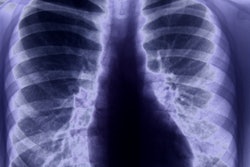

Dean Gillespie, 24, demonstrated high blood pressure readings and an enlarged heart on x-rays, which were acquired after he was stabbed in 2012. Two years later, he died after collapsing suddenly at his home.